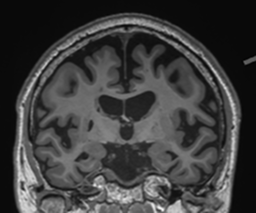

Retrospective brain volumetric analysis in a female patient diagnosed with Alzheimer’s disease at age 77 showed progressive brain atrophy over a 5-year period. The scans demonstrate both hippocampal volume loss and a clear left–right asymmetry.

Retrospective brain volumetric analysis in a female patient diagnosed with Alzheimer’s disease at age 77 showed progressive brain atrophy over a 5-year period. The scans demonstrate temporal cortical atrophy with marked ex-vacuo enlargement of the lateral ventricles.

Age 72

Age 76

Age 77

Age 74